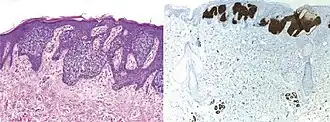

BerEp4 (also Ber-EP4) is a histologic stain mainly used to aid in the diagnosis of basal cell carcinoma (BCC).[2] It is an antibody to EpCAM (epithelial cell adhesion molecule).[1]

BerEp4 has a high sensitivity and specificity in being positive only in BCC cells.[1] BerEp4 is normally negative in squamous epithelium and mesothelium, but otherwise normally positive most epithelial cells of the body.[3] It can also help in distinguishing pulmonary adenocarcinoma (positive BerEp4) from mesothelioma (generally negative BerEp4).[3][4]